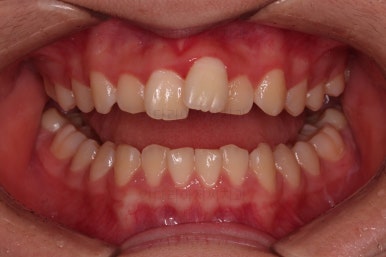

가지런한 느낌은 좋아졌고, 과개교합도 깔끔하게 개선이 되었습니다.

교합이 개선됨에 따라 자연스럽게 중앙선도 좋아지고 있는 부분이 눈에 띄고요.

부정교합이 정말 많이 좋아졌습니다.

좀 더 디테일을 맞추고 치료를 종료하기로 했습니다.

종료 때의 사진입니다.

가지런하고, 교합도 좋으며 과개교합이나 앵글씨 2급 부정교합 부분도 완벽히 좋아졌습니다.

자연스럽게 중앙선도 매우 좋아졌고요.